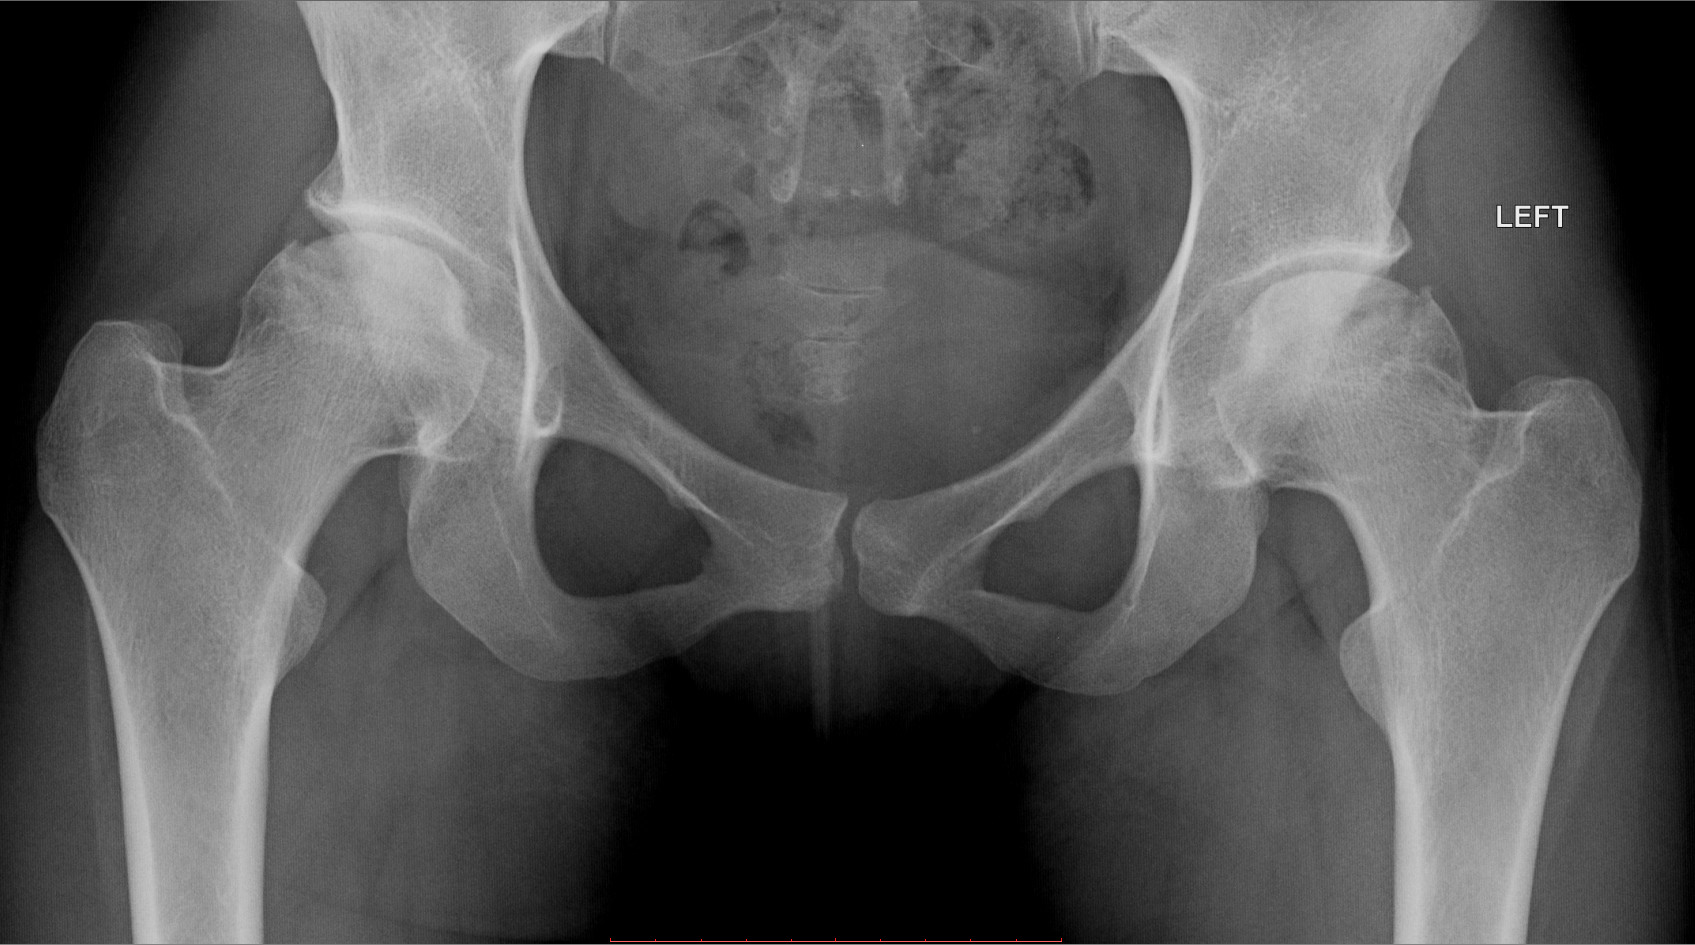

Некроз тазобедренного сустава: Фотографии и особенности лечения